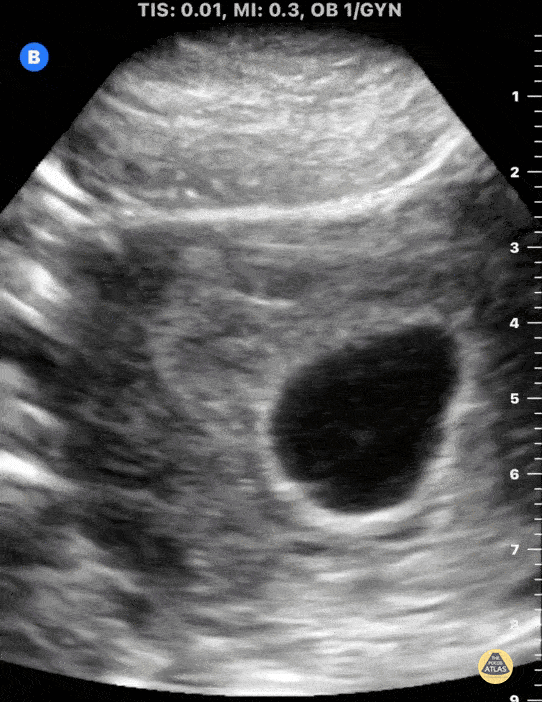

This is a transverse uterus view in early pregnancy demonstrating a a fetal pole with visualized cardiac activity. Mike Macias, MD, Emergency Physician, @emedcurious